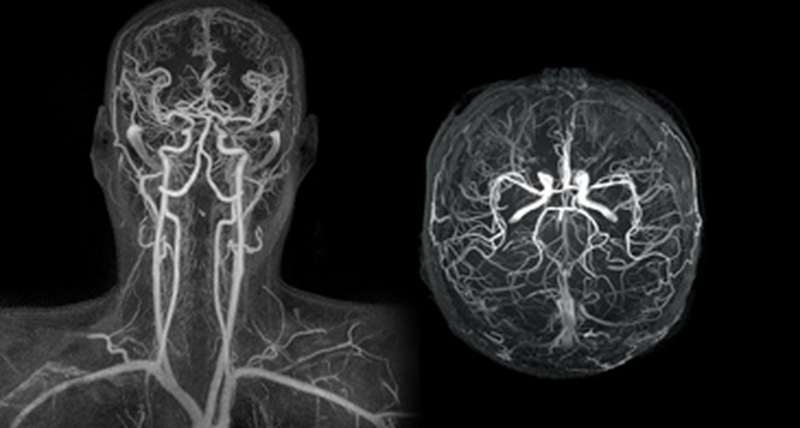

Μαγνητική Αγγειογραφία (MRA)

Η Μαγνητική Αγγειογραφία (MRA) είναι μια μη επεμβατική εξέταση που χρησιμοποιεί τη μαγνητική τεχνολογία και τους υπολογιστές για να δημιουργήσει λεπτομερείς εικόνες των αγγείων στο εσωτερικό του σώματος, συμπεριλαμβανομένων των αρτηριών και των φλεβών.